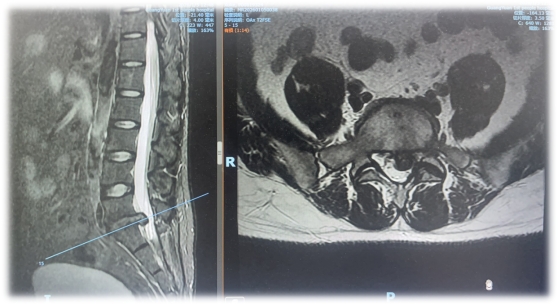

当日下午,在医院中心手术室,朱斌教授开展沉浸式示范教学,进一步深化教学效果。此次演示针对一名腰椎间盘突出症复发的中年患者。该患者2年前曾在外院接受椎间孔镜手术,术后1年再次出现左下肢疼痛、麻木症状,生活质量受影响。手术中,朱斌教授通过两个不足1厘米的切口,在水介质清晰视野下,熟练运用镜下磨钻、咬骨钳等器械,精准切除增生黄韧带及肥大关节突,完成椎管充分减压。整个手术过程解剖层次清晰、操作规范流畅、出血量少,达到预期治疗效果。